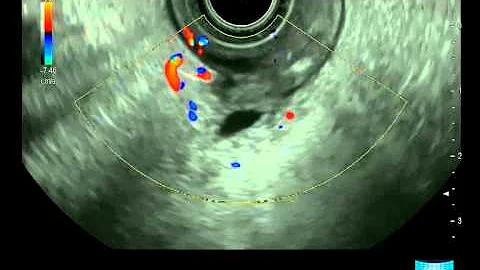

Eus - Endoscopic Ultrasound

Endoscopic Ultrasound (EUS) is now offered at Sentara Northern Virginia Medical Center. EUS offers doctors a chance to view ...